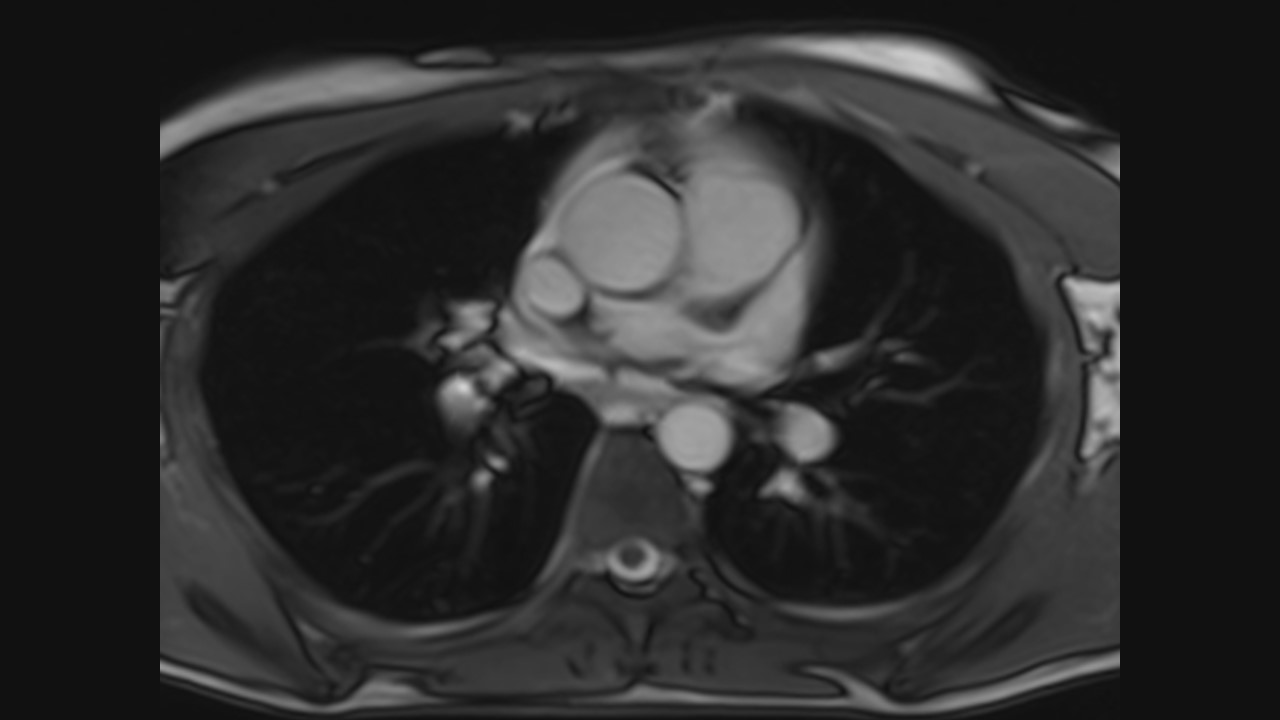

Axial Series